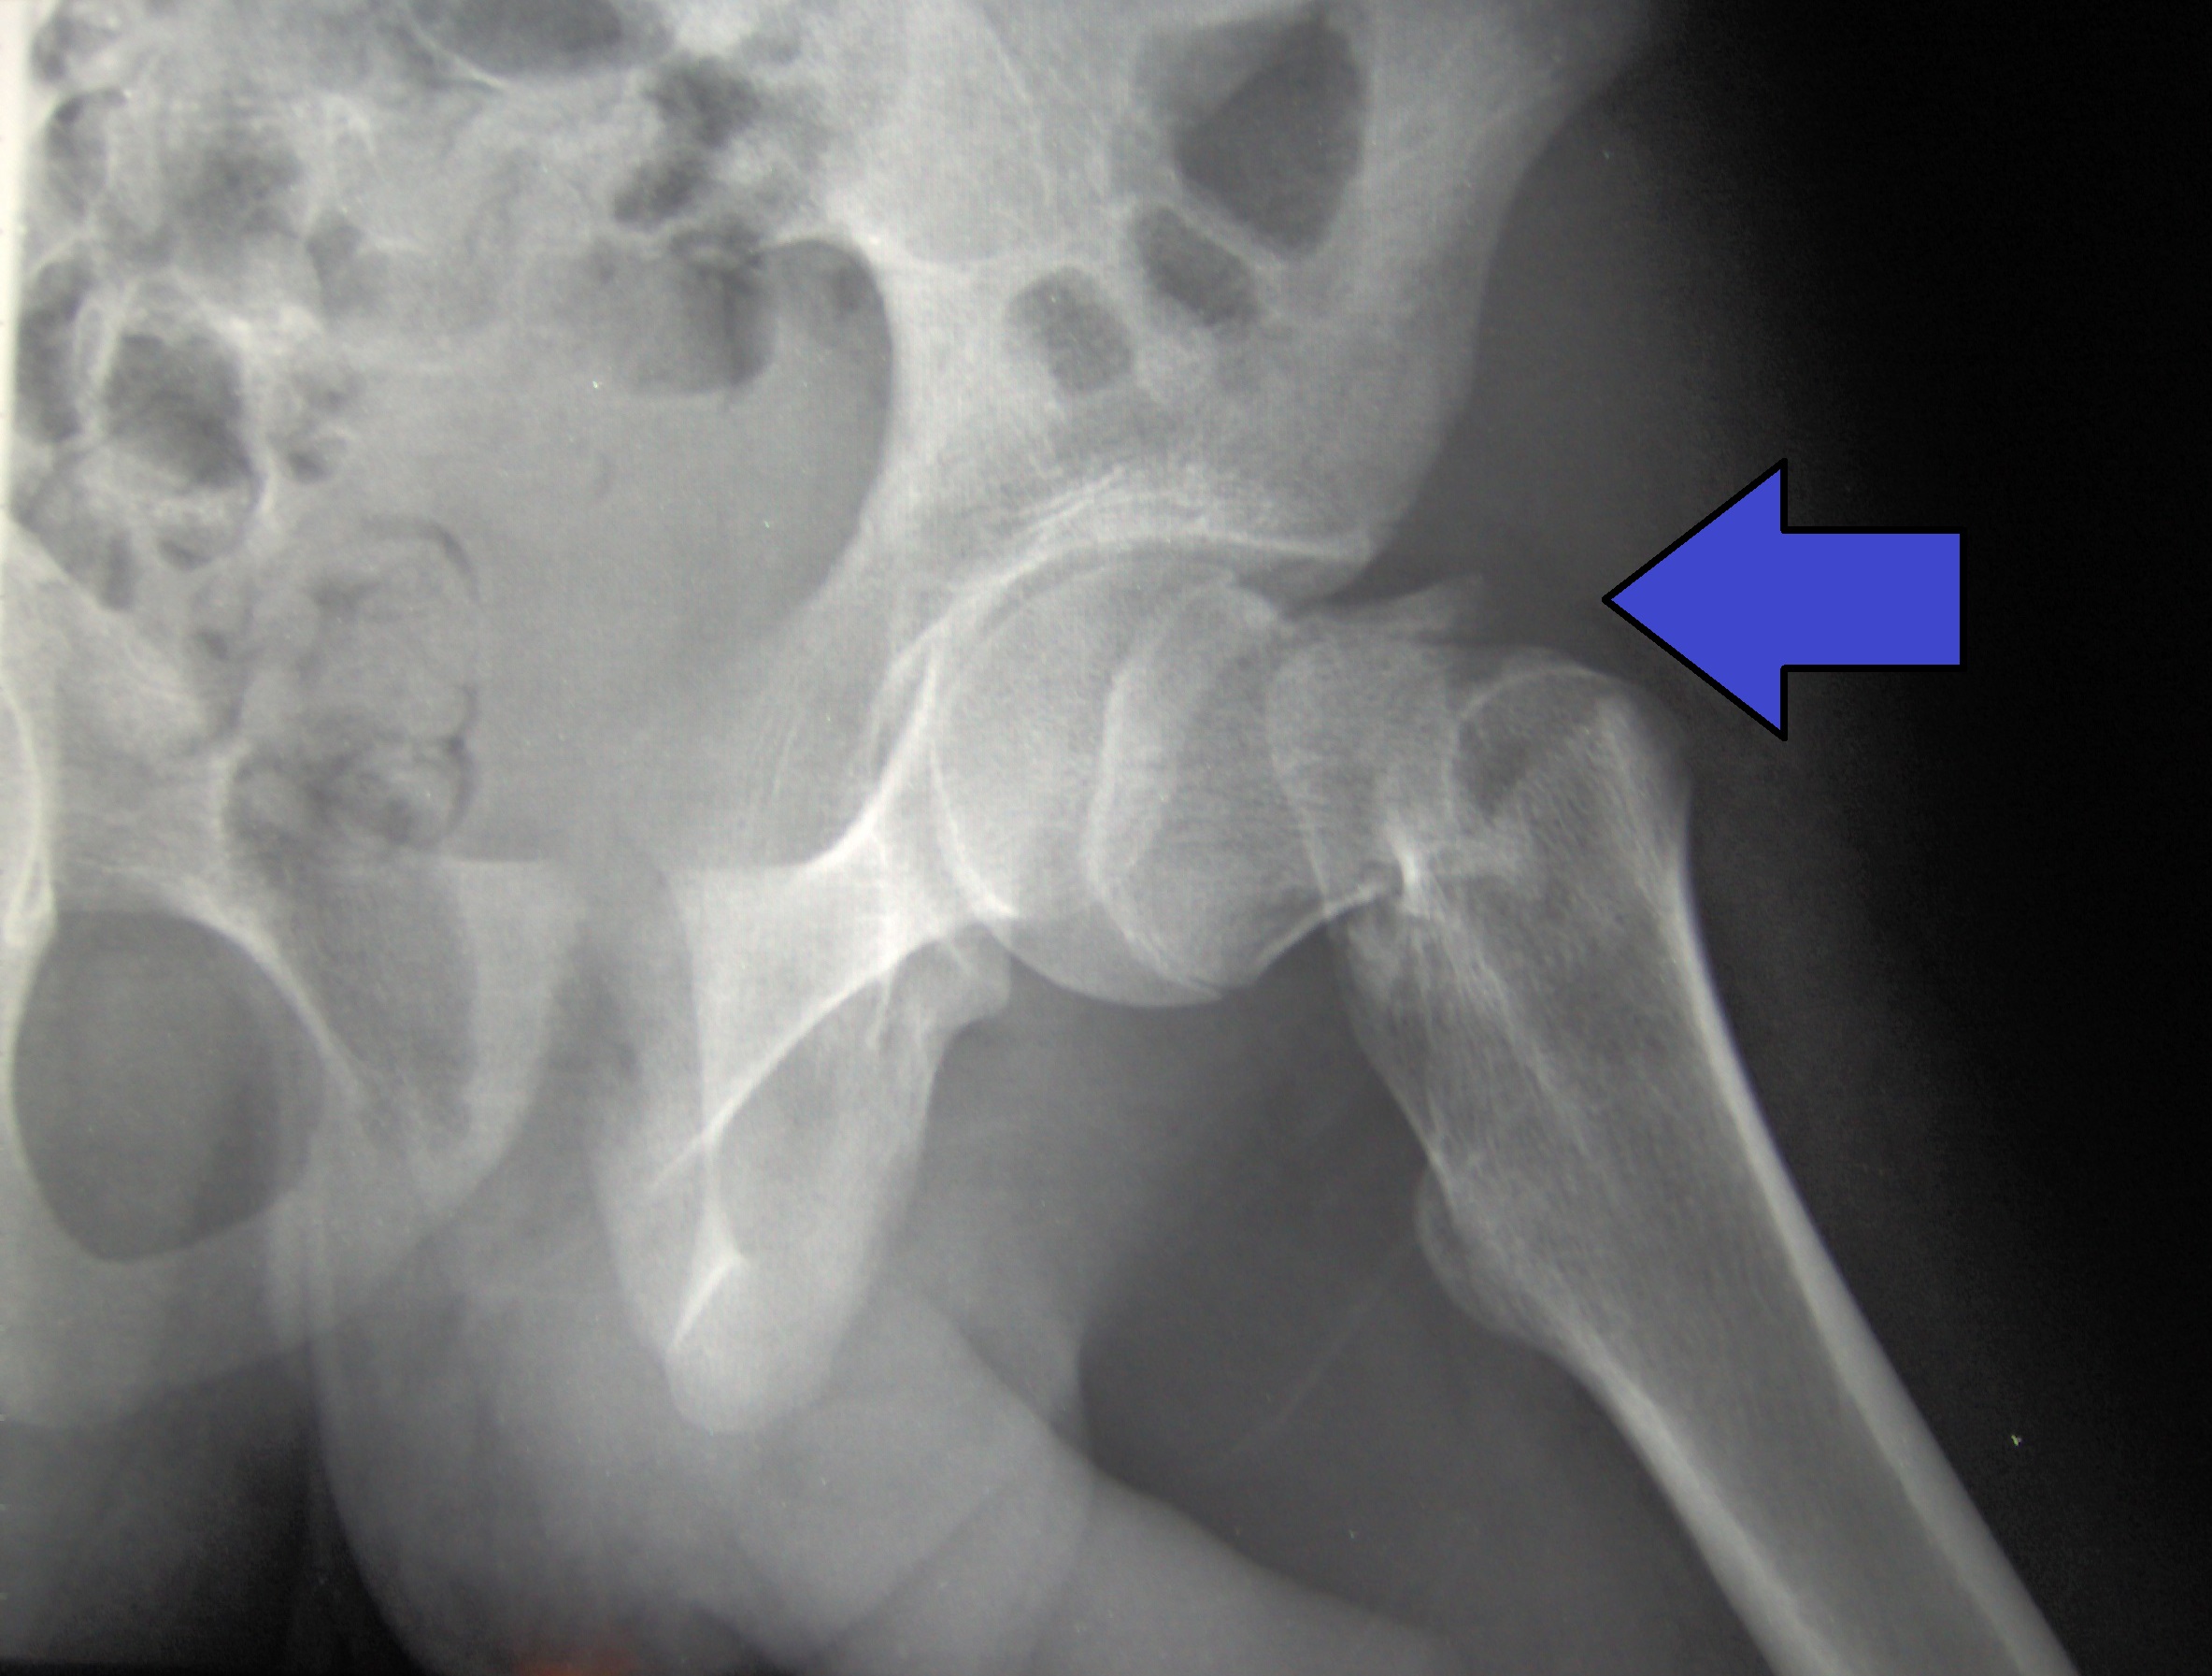

La suplementación con vitamina D no reduce la tasa total de desarrollo de fracturas en la población anciana sana, y puede aumentar la incidencia de fracturas de cadera entre mujeres ancianas sanas. Este hallazgo sugiere abstenerse de prescribir dosis intermitentes altas de vitamina D, sin calcio, a personas de 60 años o más con concentración sérica de vitamina D o estado de osteoporosis desconocidos y una ingesta inadecuada de calcio. Journal of General Internal Medicine, julio de 2024.

La suplementación con vitamina D no reduce la tasa total de desarrollo de fracturas en la población anciana sana y puede aumentar la incidencia de fracturas de cadera entre mujeres ancianas sanas. Este hallazgo sugiere abstenerse de recetar dosis altas e intermitentes de vitamina D, sin calcio, a personas de 60 años o más con concentración sérica de vitamina D desconocida o estado de osteoporosis y una ingesta inadecuada de calcio. J Gen Intern Med, 12 de julio de 2024